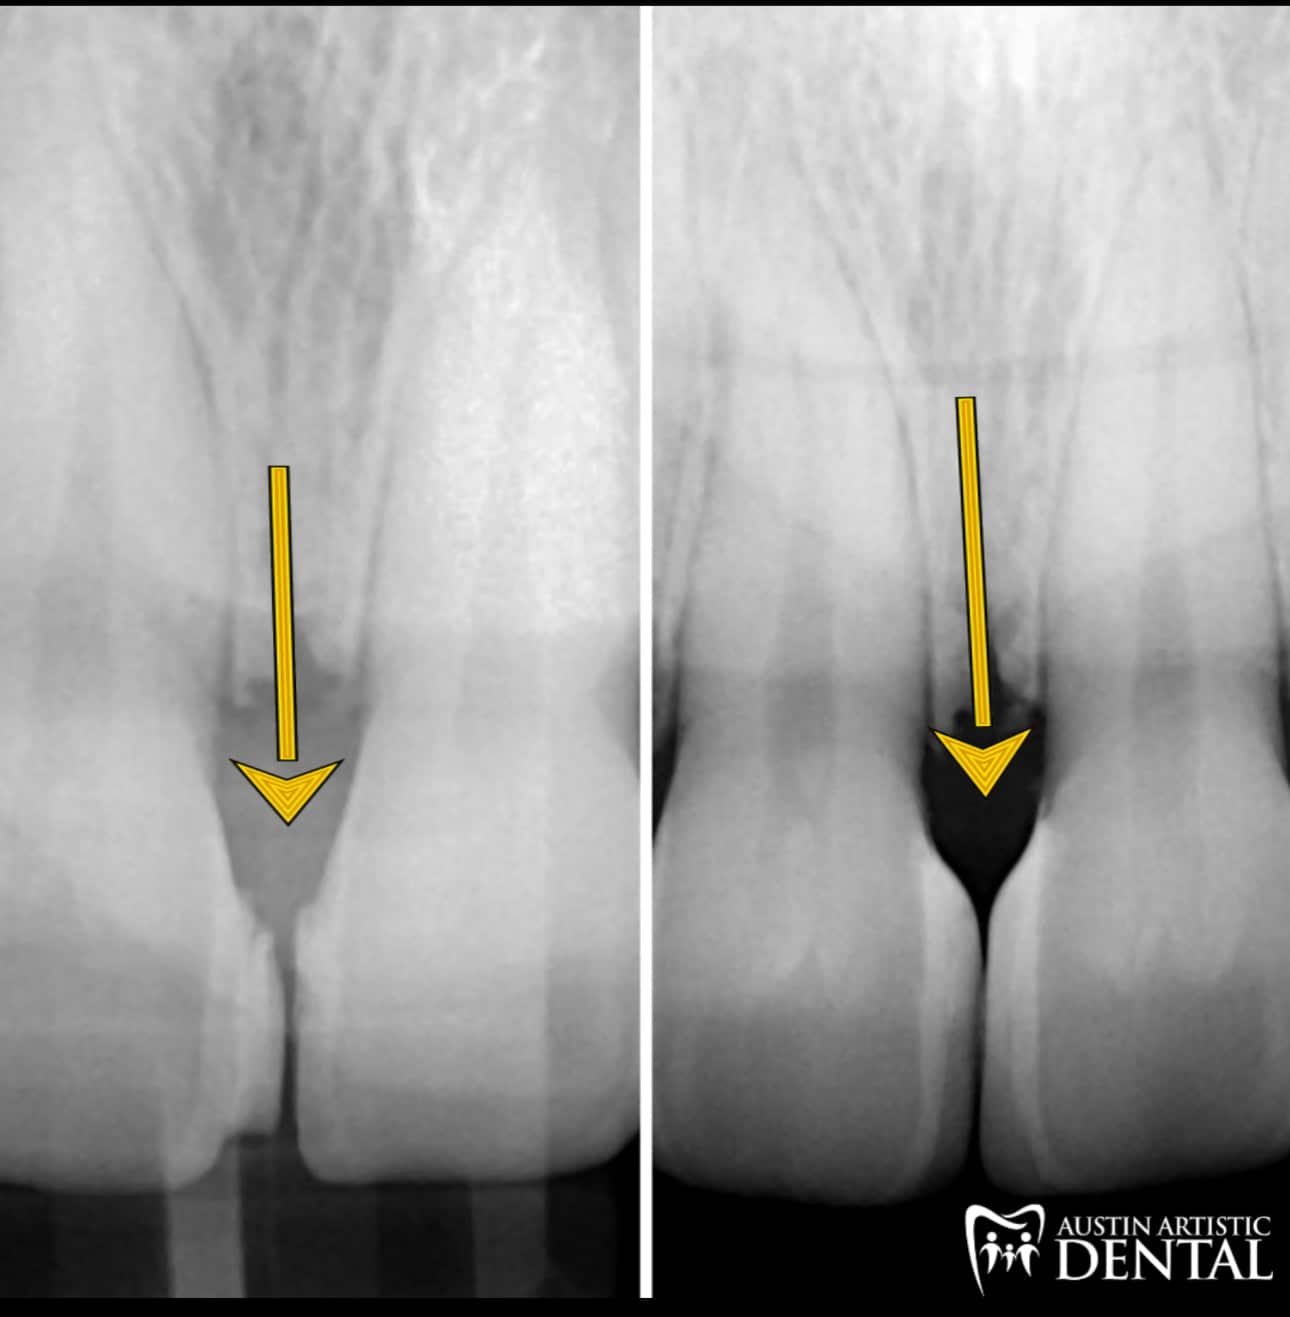

Bioclear is the best way to fix black triangles.

As we age, after braces, with gum and periodontal disease spaces often form near the gums. Some people hate these! Food gets caught all the time, and it’s the first thing they see when they smile. There is no better way to close these spaces than with Bioclear.

Below are examples of closing spaces that are called “Black Triangles”. Many people get these dark spaces between their teeth as they age, or after gum surgeries. Spaces between teeth after braces is another common place to see these “Black Triangles”. Patients may have been told in the past that these couldn’t be fixed. Or if a fix was attempted, they often become food traps, collecting plaque and food everytime one eats. Now with the Bioclear Method, these can be fixed conservatively and predictably. To learn more

you can visit our whole page dedicated to Black Triangle Closure at the link here.

Traditional Bonding techniques are often used by other dentists for fillings and close spaces. Often one will see stains and overhangs/ledges that trap bacteria and stains.

The Bioclear method doesn't just look good, but it is healthier for the gums and teeth because it is polished and smooth allowing one to floss normally, maintaining health and beauty.